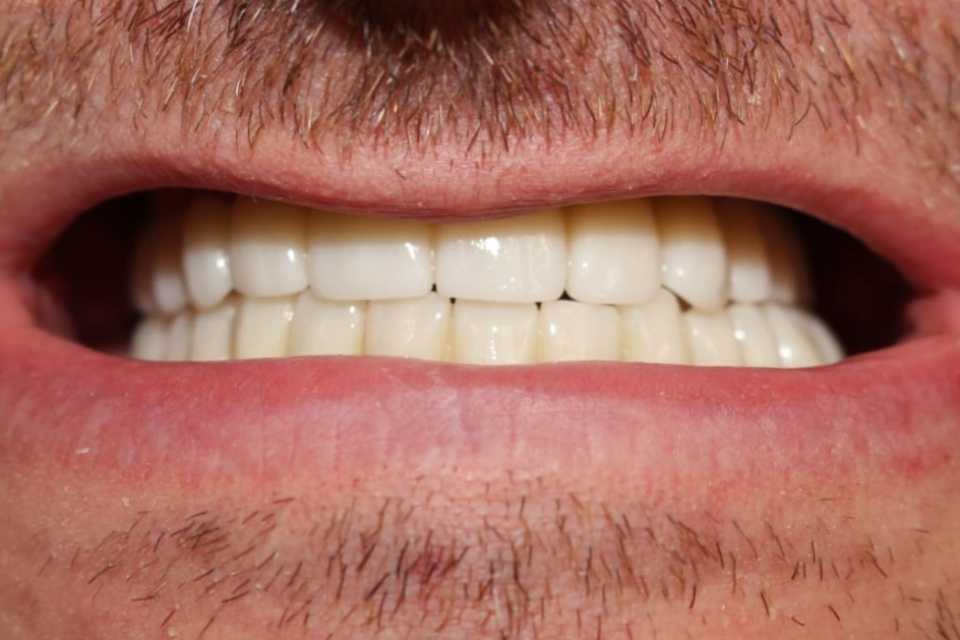

Lucrări fixe cimentate la nivelul maxilarului din ceramica pe zirconiu

Reabilitarea orala funcțională și estetică, s-a realizat cu ajutorul unei lucrări fixe cimentate la nivelul maxilarului din ceramica pe zirconiu și a 3 lucrări din ceramica pe zirconiu fixe cimentate la nivelul mandibulei.